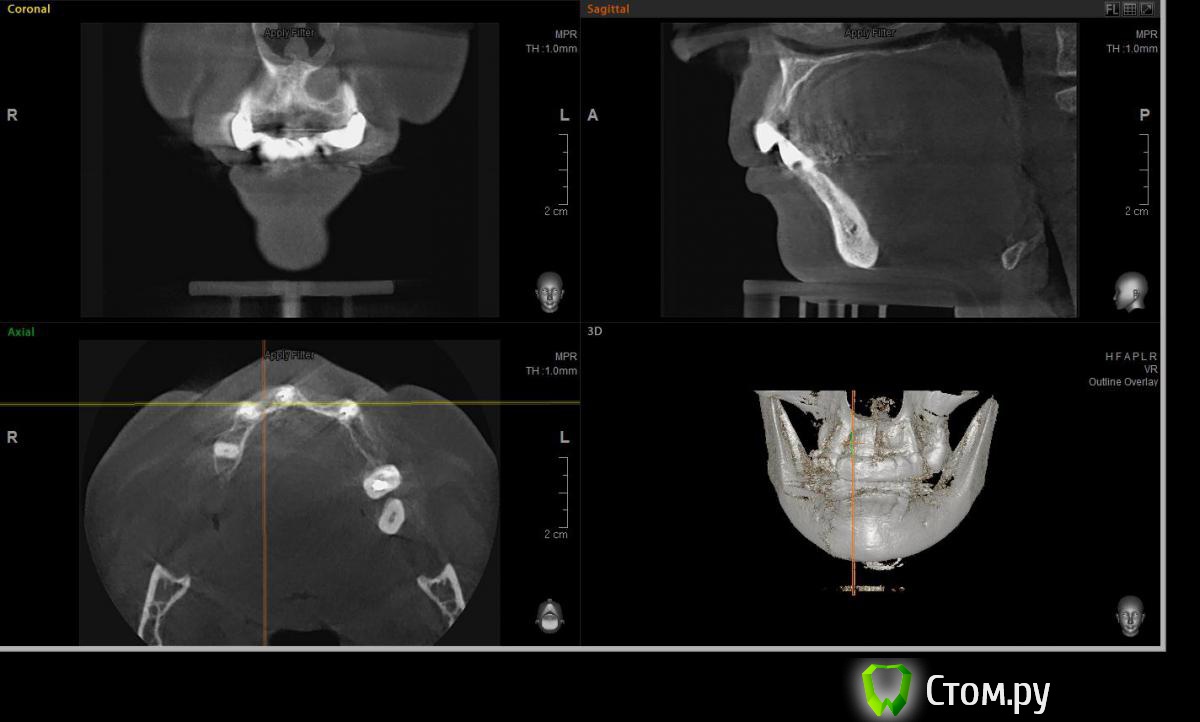

Евгений Ходыкин Опубликовано 22 июля, 2014 Автор Поделиться Опубликовано 22 июля, 2014 Дабы не плодить тем решил очередной случай выложить сюда Решили с пациенткой пока начать с в.ч. В планах имплантация в область отсутствующих 1.6, 1.4, 1.2, 2.1, 2.2, 2.4, 2.5. С 1.6 самому более менее все понятно, мануальных навыков хватит) Прошу помощи коллег относительно остальных областей. Фронт особливо печален... Забегая наперед скажу, что блоки еще не делал. Ауто точно пока брать не планирую, ибо нет даже теоретических навыков. Хочу начать все-таки с аллоблоков. У кого какие будут мнения, заранее спасибо) Ссылка на комментарий